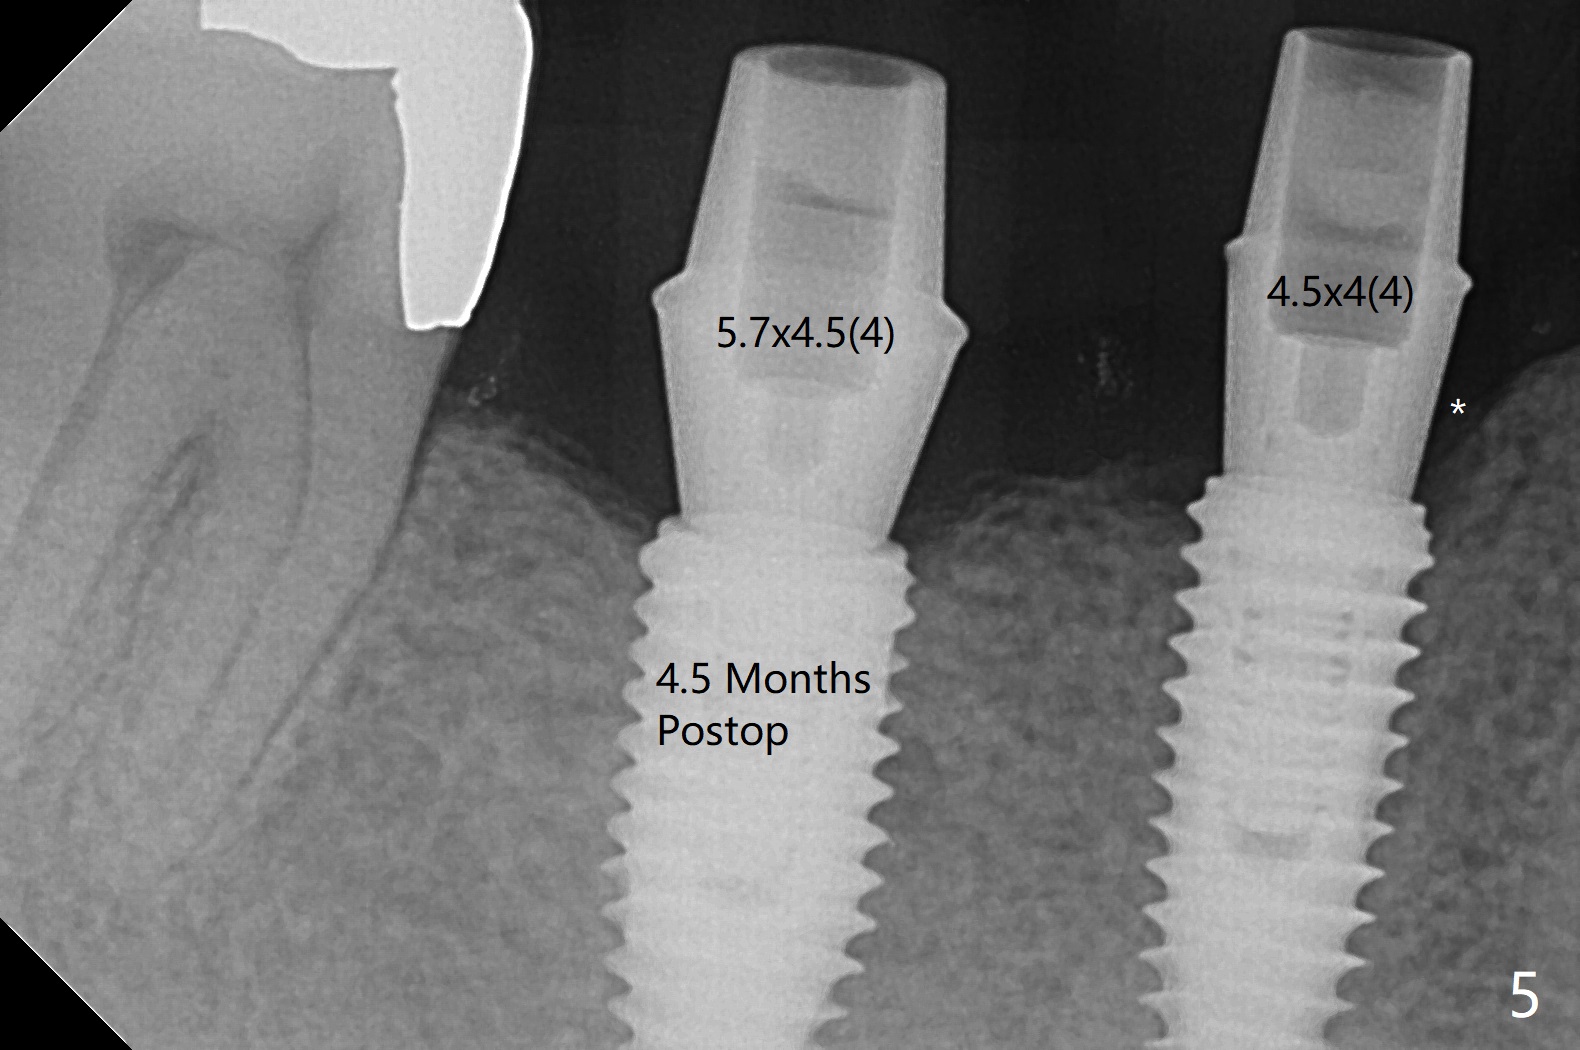

PA is taken after a 2.2 mm drill reaches depth of 11.5 mm with 10.5 mm offset at #29 to confirm that the curved apex of the neighboring tooth is not violated (Fig1 * (red line: Mental Loop)). The rest of the procedure is smooth except that the abutment at #29 is later changed to 4.5x4(4) mm (Fig.2,3 (red dashed line: Mental Loop)). The latter is easier for immediate splinted provisional and also has clearance from the crestal bone (Fig.5 *). Bone resorption seems to be minimal 4 months postop (Fig.4). The change in the abutment in cuff length (from 5.7x4.5(3) to (4) mm) at #30 eliminates the gag between the implant and abutment (Fig.4 <, as compared to Fig.5) before impression.